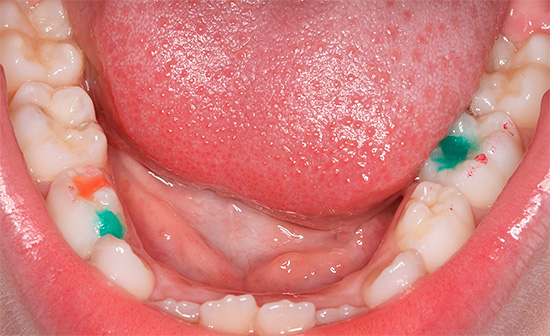

La foto mostra un esempio di argentatura dei denti da latte:

Ecco alcune altre foto di denti argentati:

Le otturazioni colorate oggi utilizzate sono composte da compomeri che rilasciano fluoruri nel tessuto dentale, come i cementi vetroionomerici, ma sono molto stabili ed estetici, come i compositi fotopolimerizzabili. Il loro fascino principale risiede proprio nei colori vivaci del materiale, che affascinano i bambini e rendono l'intera procedura simile a un gioco.

Questo è vero per i bambini di età superiore ai 4-5 anni che possono competere con i coetanei e mostrare le loro otturazioni colorate. Pertanto, il trattamento della carie in bottiglia si trasforma in intrattenimento e il medico ottiene un bambino calmo su una sedia.